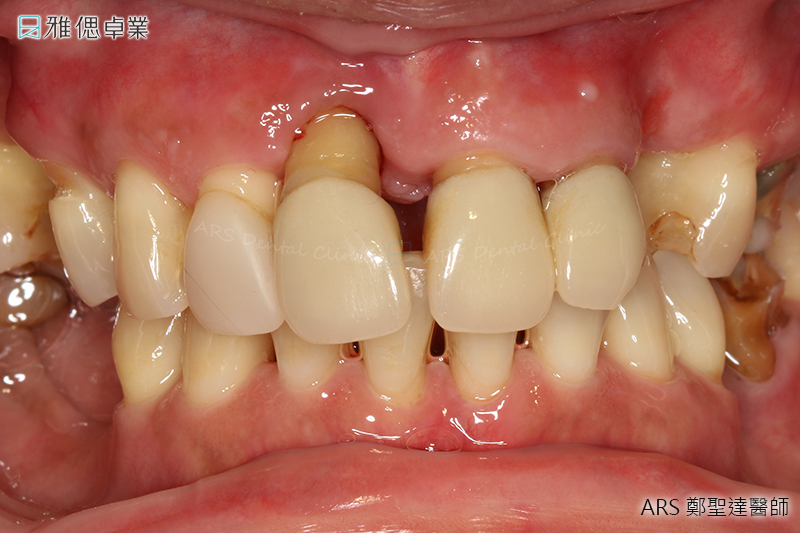

牙周治療後,會有下列情形

① 因為發炎而腫脹的牙齦經治療消腫後,變得較健康且結實,有部分牙齦會有退縮,且因骨頭高度降低而不會還原

治療過後,由於牙齦退縮,牙根外露,有些牙齒對於冷熱、某些水果、甜食會比較敏感,這種情形通常三~四天會漸漸改善,少數人可能要一~二個月

② 會搖動的牙齒治療後,可能還是會搖,這是因為地基本來就太少的原因,但功能上不會有太大的影響